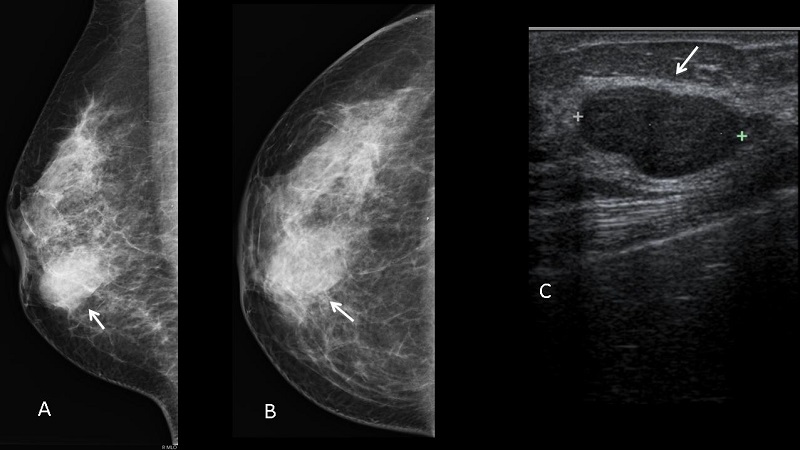

Các triệu chứng của u xơ tuyến vú nhìn chung không có tính chỉ điểm mà tương tự như biểu hiện của các loại u vú khác (bao gồm cả những trường hợp ác tính). Vậy nên ngoài các dấu hiệu lâm sàng, bác sĩ còn sử dụng thêm xét nghiệm hình ảnh để chẩn đoán bệnh, như là: